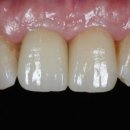

보존의 정석 스노우치과의원 서울특별시 서초구 강남대로 557 성한빌딩 5층 스노우치과 ‘스노우필름’으로 완성하는 맞춤형 심미보철 하얗고 가지런한 치아는 자신감 있는 인상을 결정짓는 중요한 요소입니다. TV에 나오는 연예인들처럼 정돈된 치아 라인과 자연스러운 톤을 가진 미소는 더 이상 특정인만의 것이...

스노우치과(논현역8번출구)(2025-06-09 11:30:00)